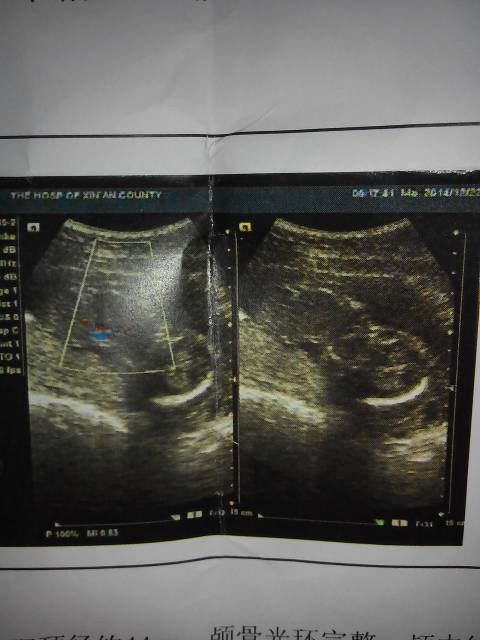

麻烦懂得帮我看看,这胎儿有手脚么 点击展开 玮晨妈妈 2014-12-25 08:47 为您推荐: 其他回答 从你给的这个B超单上是判断不出来的,因为你那个单子拍到的照片是宝宝的头部,建议你等到怀孕二十到24周的时候做一个四维彩超的检查。 个性化hao123 2014-12-25 12:51 相关问题 做四维彩超30周4天宝宝手脚偏短3周,麻烦你帮我看看正常吗?非常感谢! 昨天去医院做四维 医生什么都没说 就说还好 我感觉那个医生不专业 麻烦懂得帮我看看 孕妇肚皮痒,长了很多红点,有图,麻烦懂得帮我看看是什么